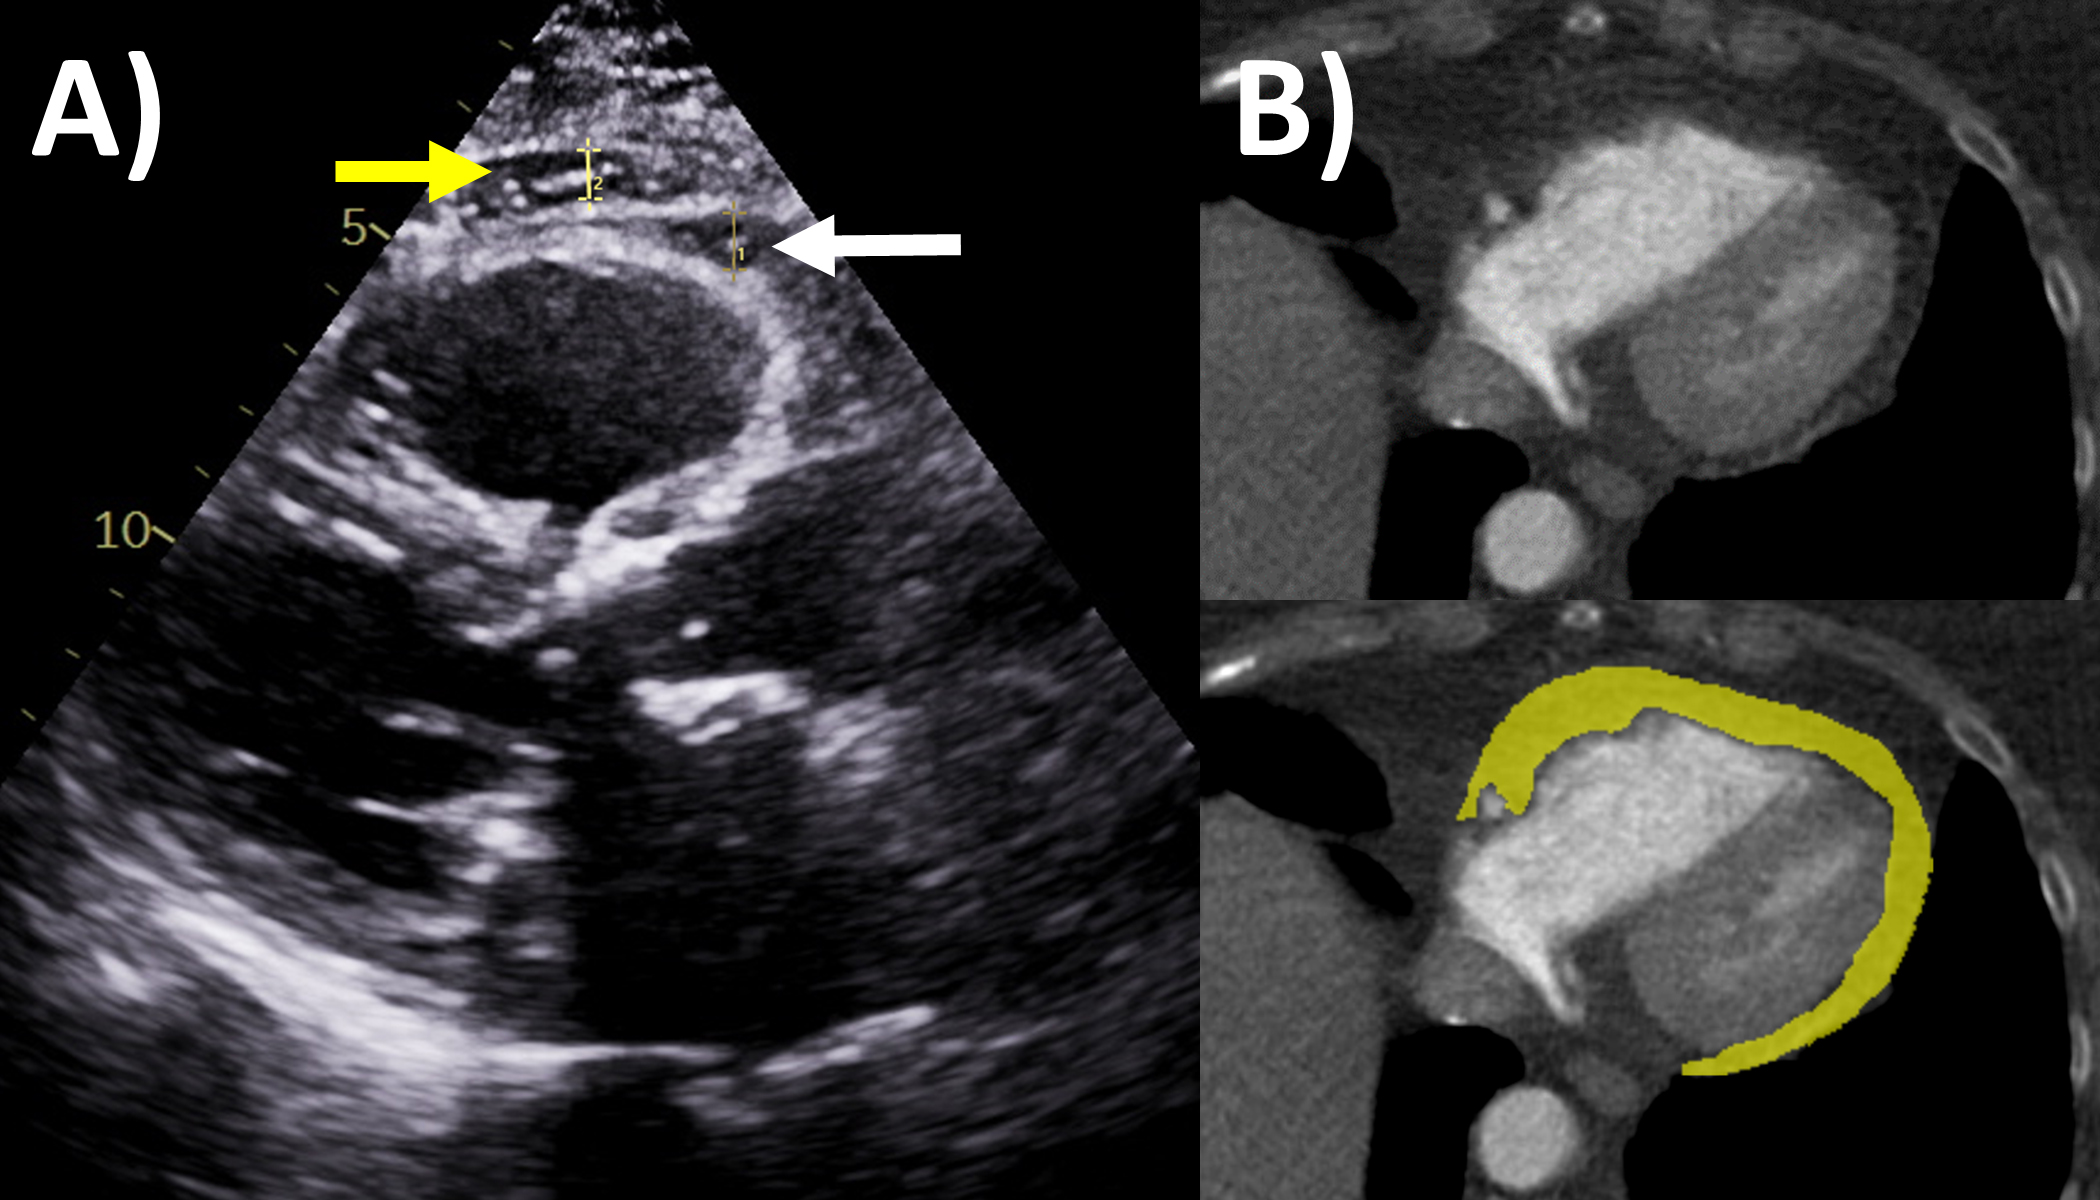

Fig. 1.Multi-modality imaging features of acute pericarditis case. (A) Small pericardial effusion (arrow) subcostal view of echocardiography. (B) Pericardial thickening (arrow) on black-blood spin echo sequence of magnetic resonance imaging (MRI). (C) Severe circumferential increased pericardial signal indicating edema (arrow) on T2-weighted short tau inversion recovery imaging of MRI. (D) Severe circumferential pericardial enhancement indicating inflammation/fibrosis (arrow) on delayed gadolinium enhancement sequence of MRI.

Perhaps the most important application of MRI in pericardial diseases is its ability to identify pericardial inflammation [2, 10]. The key features include pericardial thickening, best assessed on black-blood spin echo sequences; pericardial edema, assessed using T2-short tau inversion recovery (STIR) sequences as high signal intensity; and inflammation or fibrosis on late gadolinium enhancement sequences again as high signal intensity (Fig. 1) [2, 13, 14]. Histologically, pericardial late gadolinium enhancement correlates with fibroblastic proliferation, neovascularization and chronic inflammation and granulation tissue [15]. Some studies have reported moderate sensitivity (63–68%) and high specificity (up to 100%) of the T2-STIR sequence for acute pericarditis, however this is significantly lower in practice, as elevated signal can also be seen with pericardial effusion or MRI artefact [16, 17]. The delayed enhancement sequence has been reported to have moderate to high 65–100% sensitivity and high specificity 99–100% for pericarditis, however again in practice this is lower with pericardial fat, pleuritis and artefact potentially interfering with scan interpretation, and fat saturated pulses added to delayed enhancement sequences are recommended to improve the positive predictive value of pericardial enhancement [14, 16, 17, 18]. MRI can also evaluate for concomitant myocardial involvement and inflammation (myocarditis) where they be left ventricular dysfunction and regional wall motion abnormalities on cine sequences; increased myocardial signal intensity on T2-STIR or elevated T2-mapping values implying myocardial edema; increased myocardial signal intensity on delayed gadolinium enhancement sequences or elevated T1-mapping values consistent with myocardial inflammation and fibrosis; and along with early gadolinium enhancement suggesting hyperemia [19]. As such MRI is strongly recommended in the initial diagnosis of pericarditis with a complimentary role to clinical, inflammatory biomarkers and echocardiography assessment, especially if the diagnosis remains uncertain after the other tests [1, 2, 10].